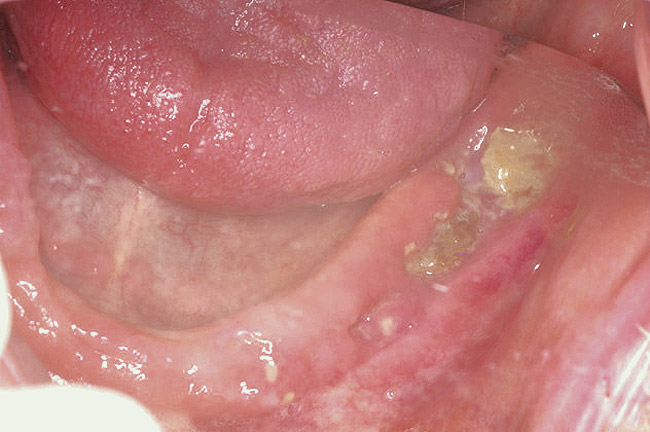

For patients on IV bisphosphonates, after bone is exposed, it is almost impossible to cover.15 Most cases worsen if surgical intervention is performed. Most patients must simply deal with the exposed bone and keep it clean so that bacterial infection does not occur. Figure 2 and Figure 3 show a postmetastatic prostate cancer patient with exposed bone. The treatment plan for this patient was to make a soft-lined denture that would not put pressure on the exposed bone and to check for bacterial infection on a routine basis. When dealing with patients on or about to begin IV bisphosphonate therapy, dentists need to be very astute. As stated earlier, this form of the drug has a much higher incidence of complications. These patients are often very sick and immuno-compromised and, therefore, must be managed properly. Pre-IV bisphosphonate patients (ie, those not yet receiving the drug) are much easier to manage than patients already receiving the drug. First, ask the treating physician, usually an oncologist, if he or she can wait 2 months before the drug is given. If the cancer is severe, it may not be possible to wait. Dental healthcare provides should make use of whatever time can be made available before bisphosphonate treatment begins.16 This time should be used to get a full-mouth series of radiographs and to remove all dental infections, including all decay. If decay cannot be removed completely, the tooth should be considered for extraction. Before IV therapy begins, patients are at a lower risk for extraction complications than they are during bisphosphonate therapy.

Figure 2  Postmetastatic cancer patient with BRONJ (A) in the lower right quadrant and (B) in the lower left quadrant.

Figure 2

Figure 3  Postmetastatic cancer patient with BRONJ (A) in the lower right quadrant and (B) in the lower left quadrant.

Figure 3